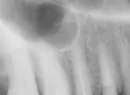

Пять дней назад врач перелечивала мне 15-й зуб, который депульпировали в январе, но он продолжал болеть. Не запломбировано 1,4 мм до апекса, ноет также скуловой нерв и висок. Чистила канал, затем с неохотой, потому что я настояла, сделала снимок с файлом. Но снимок мне кажется неубедительным, так как не видно, ни верхушки зуба, ни конца файла. Однако врач сказала, что видно все что надо. Сделала еще один снимок опять точно такой же (слепой).

Создалось впечатление, что врач не хочет, чтобы я увидела весь корень. Потом еще что-то чистила в канале и сказала, что канал на конце загибается. В конце положила лекарство на 2 недели и поставила временную пломбу. Боюсь, как бы ни было перфорации возле апекса (тем более, что вплотную к зубу пазуха), а врач это скрыла.

Насколько информативен этот снимок с файлом? Надо ли просить врача на следующем приеме перед началом пломбирования канала все-таки сделать хороший снимок с файлом?

Да, на первом фото видно, что канал запломбирован не до верхушки корня. На втором снимке канал пройден больше, но апекс отчетливо не снят. Так как пазуха близко, лечение должно проводиться очень осторожно, желательно под микроскопом и с апекслокатором.